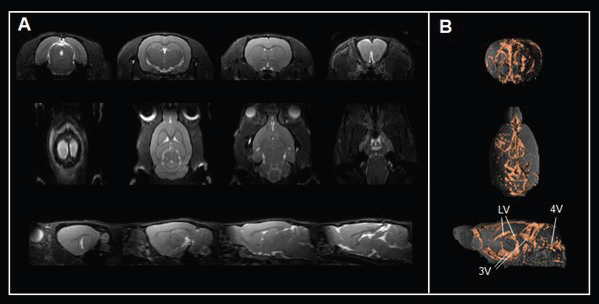

For instance, a true fast imaging with steady-state precession (TrueFISP) sequence gives contrast for cerebrospinal fluid spaces (Fig. 5A) and 3D renderings (Fig. 5B) and allows the assessment of ventricle anatomy and morphology, an important compartment for cerebrospinal fluid production and transport.

Assessing brain ventricles. A) Axial, coronal, and sagittal T2-weighted TrueFISP images and B) corresponding renderings reveal the cerebrospinal fluid spaces in the rat brain. Rat brain data was acquired with a BioSpec Maxwell 94/17 using a volume coil for transmission and a phased-array coil for reception. Tissues were segmented and rendered using PMOD. LV = lateral ventricle; 3V = third ventricle; 4V = forth ventricle

Figure 5. Assessing brain ventricles. A) Axial, coronal, and sagittal T2-weighted TrueFISP images and B) corresponding renderings reveal the cerebrospinal fluid spaces in the rat brain. Rat brain data was acquired with a BioSpec Maxwell 94/17 using a volume coil for transmission and a phased-array coil for reception. Tissues were segmented and rendered using PMOD. LV = lateral ventricle; 3V = third ventricle; 4V = forth ventricle. Image Credit: Bruker BioSpin Group